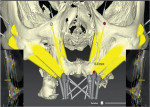

As an alternative to the quad zygoma technique, the transnasal implant technique was developed, in which implants are inserted into the basal bone of the maxilla, across the nasal cavity tangent to the distal wall, and anchored apically in the frontal process of the maxilla (Figure 1 and Figure 2).4,10,11 Using the nasal cavity walls as anchorage for implants12 increases bone availability in the anterior region of the maxilla, allowing for the installation of an anterior extra-long conventional implant accompanied by a posterior zygomatic implant (Figure 3). As long as the anatomy of the region is respected and the final positioning of the transnasal implants is appropriately planned, this technique has been shown to achieve a high success rate.11

When virtually planning transnasal implants with cone-beam computed tomography (CBCT) data and CAD software, a minimum bone height of 3 mm is required between the maxillary edge and the nasal cavity. A bone height of less than this may make immediate loading impossible. In addition, at least 3 mm of implant anchorage is required in the frontonasal process of the maxilla, which allows the extra-long implants to be anchored in good-quality bone.

The height of the alveolar ridge, the shape of the nasal cavity, and the availability of implant anchorage in the frontal process of the maxilla should be evaluated to determine if the transnasal technique is indicated, and the use of a prototype permits these criteria to be observed with greater security (Figure 4).18 The frontomaxillary pillar is found in a region where dense bone normally exists, which allows the placement of long implants with parasinusal angulation.19 Using these bone pillars as anchorage for dental implants transfixing the nasal cavity18 increases bone availability in the anterior region of the maxilla.

Patients with extensive nasal cavities that have very distal lateral limits are not indicated for the transnasal technique because the implant may not reach the distal bone wall, making bone reconstruction unfeasible and possibly interfering with respiratory function. In addition, detailed anatomical knowledge of this region is necessary due to the proximity of the internal maxillary artery in the frontozygomatic process, the nasolacrimal duct, and the posterior palatine artery.20